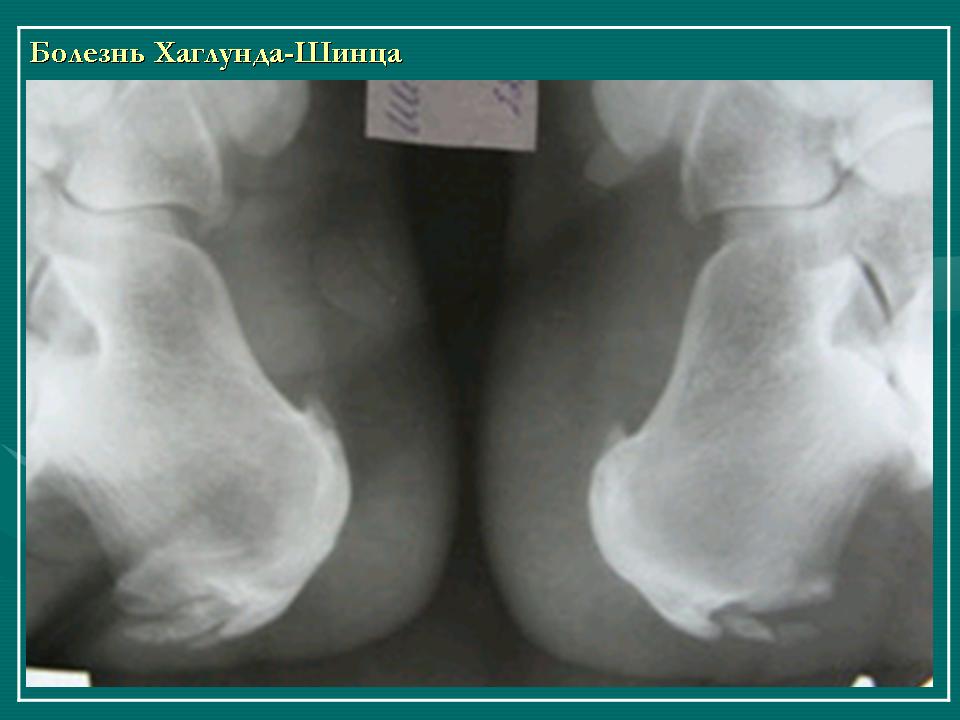

На рентгенограммах, особенно в боковой проекции, определяется уплотнение апофиза, расширение щели между апофизом и пяточной костью. Трудности рентгенологической диагностики связаны с тем, что в норме апофиз пяточной кости у детей имеет до 4-х ядер окостенения, среднее из которых, как правило, уплотнено, а смежные поверхности пяточной кости и апофиза зазубрены.

Наиболее характерным рентгенологическим признаком остеохондропатии является пятнистая структура уплотненного ядра окостенения. В дальнейшем наступает фрагментация апофиза, а затем и его перестройка - формируется новое губчатое вещество кости.